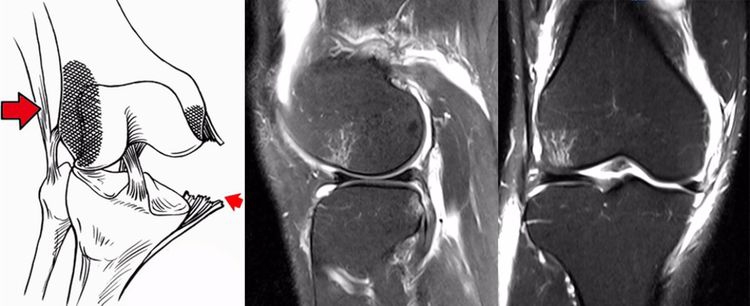

ACL损伤的间接征象:指ACL断裂后胫骨前移位出现的一系列改变。间接征象只能考虑可能有ACL损伤。

1.骨挫伤(轴移征):一旦ACL撕裂,胫骨就相对于股骨前移,使股骨外侧髁和胫骨外后方撞击,双方均出现水肿,而且膝关节屈曲的程度决定股骨髁挫伤的部位。

2.沟槽征:当股骨外髁骨因撞击造成的凹陷深度>2mm时称为沟槽征,代表受到撞击的暴力更大。

3.接吻征:膝关节过伸受伤时,胫骨前部撞击股骨髁前部,形成对称性骨挫伤;如果同时有一外翻力的话,膝关节外侧可出现对称性挫伤,这种对称性骨挫伤称为接吻征。也有人把轴移造成的股骨外侧髁和胫骨外后方水肿称为接吻征。

4.Segond骨折:胫骨平台前外侧撕脱骨折(胫骨平台腓骨尖上方,关节线下方的撕脱骨折),多因为下肢过度内翻加内旋暴力所致。骨折本身无特殊治疗。但其强烈提示ACL损伤(75–100%)。

5.前抽屉征:胫骨前移,外侧半月板后角裸露,由于MRI检查时病人为平卧位,胫骨应该因重力而后沉,因此前抽屉征往往暗示膝关节处于交锁状态。